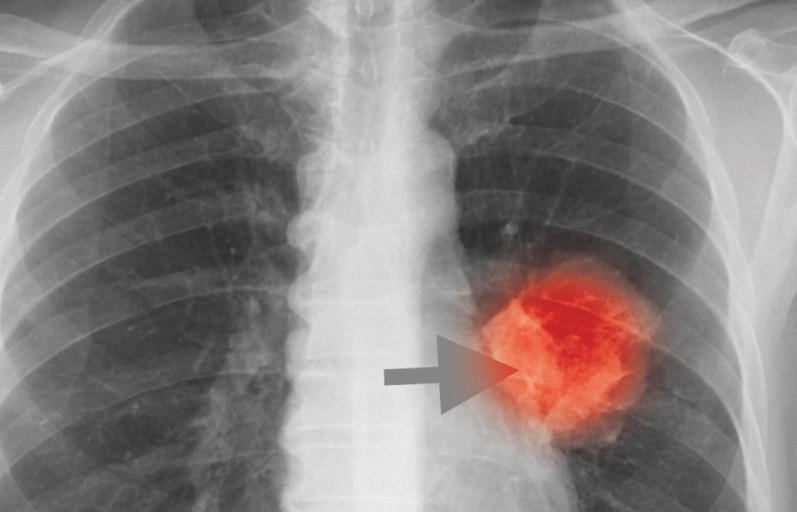

폐렴 증상 폐렴은 폐의 세균, 바이러스, 곰팡이 등 감염으로 인해

폐포(폐 속의 공기 주머니)에 염증이 생기고, 고름이나 액체가 차는 질환입니다.